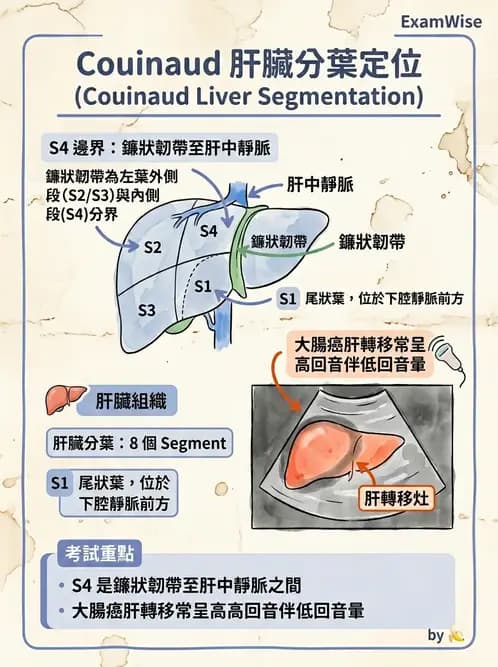

本題考查腹部超音波肝臟 Couinaud 分葉系統(Couinaud liver segmentation)的辨識,特別是在橫切面(transverse view)下如何定位各 segment 的位置。大腸癌(colorectal cancer)最常見的轉移部位為肝臟,能在超音波下精確標定轉移灶所在的 segment,對外科手術計畫及影像報告撰寫至關重要。

- 解剖定位:在橫切面上,左葉內側段(medial segment of left lobe)即 Segment 4,其解剖邊界為:

- 左側:鐮狀韌帶(falciform ligament)

- 右側:肝中靜脈(middle hepatic vein)